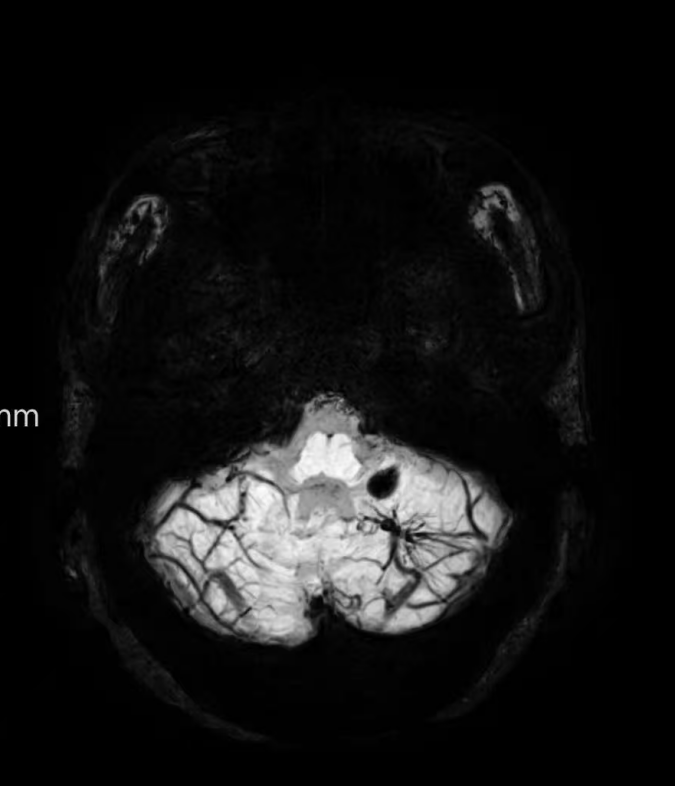

臨床中遇到一位患者,中年女性,反復(fù)出現(xiàn)頭痛,時輕時重,常規(guī)CT及磁共振檢查無明顯異常發(fā)現(xiàn),最后建議加做一個磁共振磁敏感加權(quán)成像(SWI),結(jié)果發(fā)現(xiàn)是左側(cè)小腦發(fā)育性靜脈畸形(DVA),SWI清晰顯示畸形的靜脈及周圍含鐵血黃素沉積;如下圖。這正是她頭痛的原因。

①診斷靜脈畸形:SWI能高精度地顯示發(fā)育性靜脈畸形——一種常見的腦血管畸形。在SWI上,發(fā)育性靜脈畸形會呈現(xiàn)典型的“海蛇頭”或“水母頭”征,即一堆細(xì)小的髓靜脈匯入一支粗大的引流靜脈。